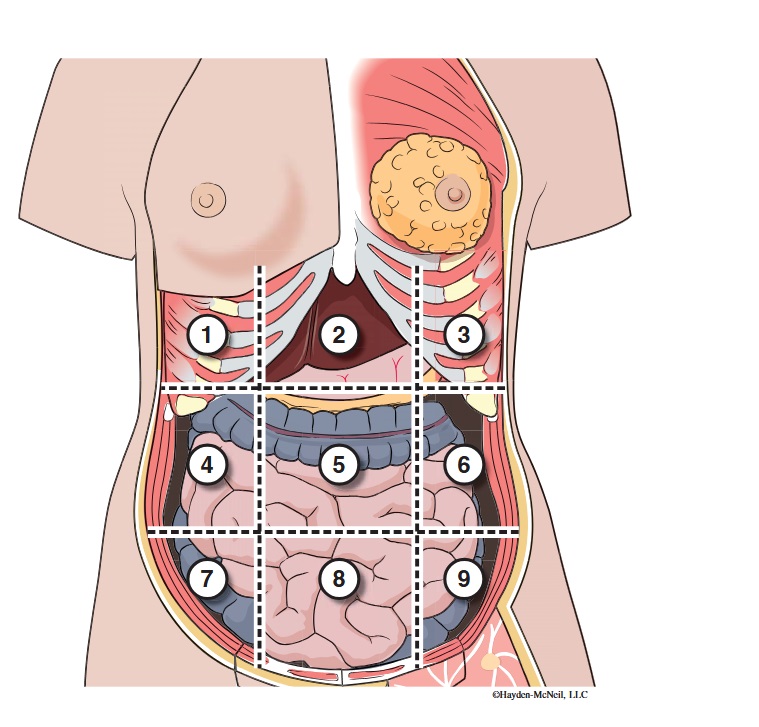

What abdominal region is labeled #1?

right hypochondriac

What abdominal region is labeled #2?

epigastric

What abdominal region is labeled #3?

left hypochondriac

What abdominal region is labeled #4?

right lumbar

What abdominal region is labeled #5?

umbilical

What abdominal region is labeled #6?

left lumbar

What abdominal region is labeled #7?

right iliac/ inguinal

What abdominal region is labeled #8?

hypogastric

What abdominal region is labeled #9?

left illiac/ inguinal

What organs are apart of the right hypochrondriac region?

right lobe of liver, gallbladder, right adrenal gland

What organs are apart of the epigastric region?

pyloric end of stomach, duodenum, pancreas

What organs are apart of the left hypochondriac region?

stomach, spleen, left adrenal gland

What organs are apart of the right lumbar region?

ascending colon, right kidney, portion of small intestine

What organs are apart of the umbilical region?

omentum, mesentery, small intestine

What organs are apart of the left lumbar region?

descending colon, left kidney, portion of the small intestine

What organs are apart of the right iliac/ inguinal region?

cecum of large intestines, appendix, right ovary

What organs are apart of the hypogastric region?

ileum, bladder, uterus

What organs are apart of the left iliac/ inguinal region?

sigmoid colon, left ureter, left ovary